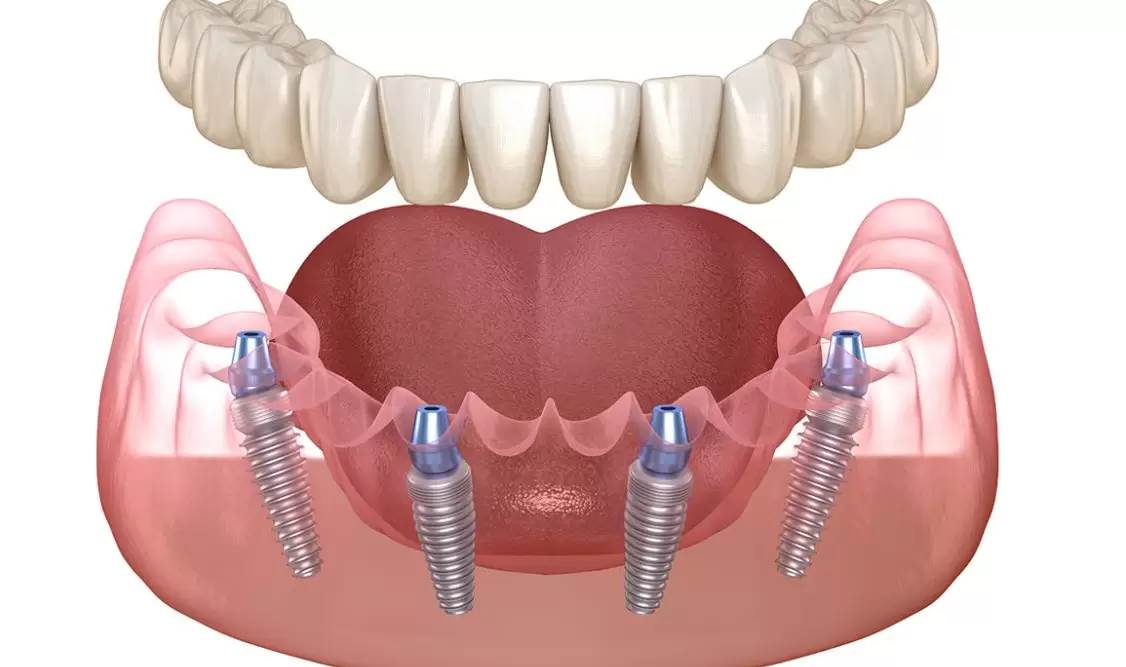

All on 4

All on 4 può creare una serie completa di denti utilizzando solo quattro impianti in ciascuna mascella. La fattibilità di ciò dipende dalla mascella e dalle circostanze specifiche. Una volta valutati i tuoi denti attuali, il livello di danno, nonché la struttura e la salute della mascella, possiamo stabilire se un impianto All on 4 è la scelta giusta. Questa procedura chirurgica utilizza otto impianti, quattro nella mascella superiore e quattro nella mascella inferiore, per supportare protesi o corone permanenti.